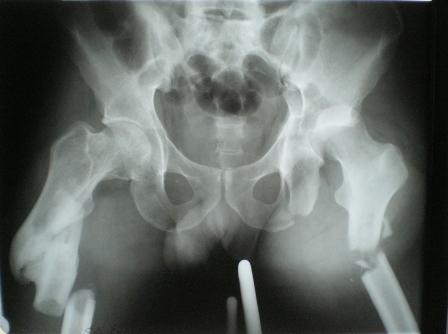

Глубокоуважаемые коллеги! Благодарю за полезные советы, которые нам очень помогли в выборе оперативной тактики пациента. 13.02.08 мы выполнили первый этап оперативного лечения этого больного. Вначале зафиксировали левое бедро АВФ Гофмана

(главный травматолог области достал из каких-то «анналов», первый раз в жизни увидел этот аппарат в живую). После наложения «ДРУ Челнокова» выполнили ЗИО правого бедра реконструктивным штифтом Chm. Далее уложили пациента на левый бок и выполнили остеосинтез вертлужной впадины. Ограничились задне-латеральным доступом без отсечения вертела, чтобы не утяжелять операцию. Результат прилагается.

Следующим этапом планируем выполнить ЗИО левого бедра.

1. укорочение левой н\конечности составляет 3 см. Необходимо ли думать об этом сейчас, или вернуться к устранению укорочения после консолидации перелома?

2. сохраняется некоторое смещение переднего отдела вертлужной впадины, нужно ли его устранить?